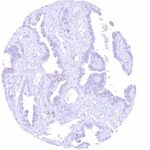

Staining Pattern in Relevant Tumor Types

PODXL expression occurs in many different tumor types.

The TCGA findings on PODXL RNA expression in different tumor categories have been summarized in the Human Protein Atlas.